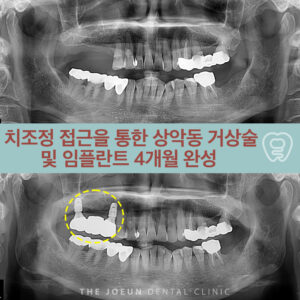

다사치과

다사치과 치조정 접근을 통한 상악동 거상술 및 임플란트 4개월 완성

다사치과 치조정 접근을 통한 상악동 거상술 및 임플란트 4개월 완성   임플란트는 치과 치료에서 가장 널리 활용되는 상실 치아를 대체할 수 있는 방법이지만 모든 환자가 수술에 적합한 조건을 갖추고 있는 것은 아닙니다. 특히 위턱 어금니 부위의 골량 부족 문제는 임플란트 시술을 어렵게 만드는 대표적인 요인으로 꼽히는데요. 이 같은 제한을 극복하기 더보기…